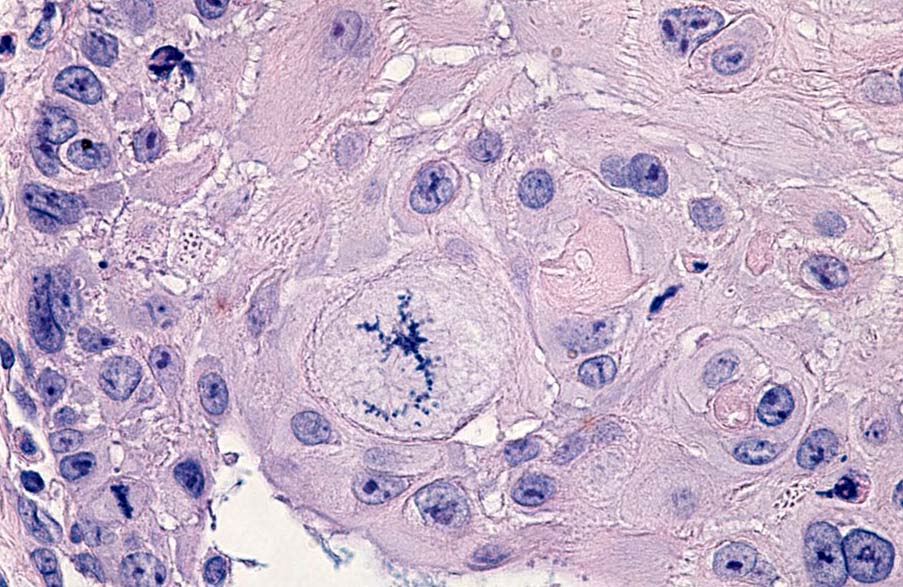

Mitosefigur in Form eines Skorpions